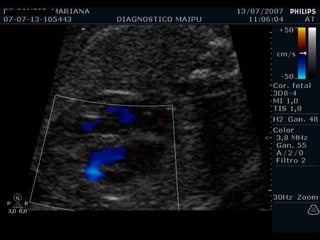

Flap